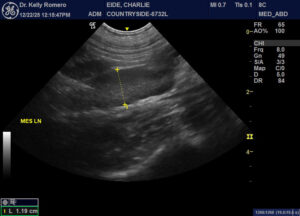

8 month old FI Golden with no clinical symptoms. pcDVM did wellness blood work one week ago- WBC was 35,000 with all cell lines elevated. Two weeks ago, owners notes some vaginal bleeding (mild). One week ago (when blood work run), vaginal discharge became more clear (still mild) and behaviorally, the male neutered dog in the house became interested and the female is receptive. Only findings I am wondering about were both ovaries appear to have active follicles (was expecting that in just one) and quite plump mes. lns. VIN search=not normal to have elevated WBC during estrus. Thoughts?

Looks like cystic ovaries and early pyometra to me and juvenile or reactive LN. OVH if not intended for breeding.